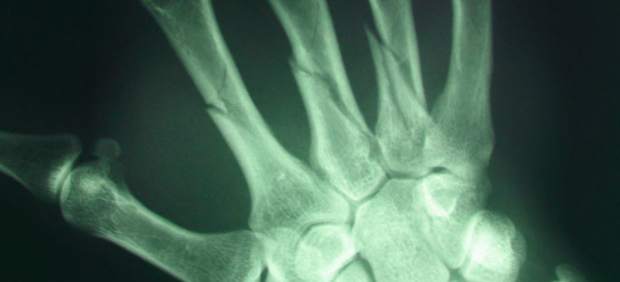

Este nuevo método, creado por el Instituto de Seguridad Industrial, Radiofísica y Medioambiental (ISIRYM), permite que cada vez que se hace una radiografía se aplique un filtro que hace la imagen más nítida, con lo que se permite que la dosis de radiación se pueda reducir de forma que el radiólogo pueda hacer el diagnóstico sin perder calidad de imagen.

Los investigadores de la UPV han creado un software que además de reducir la cantidad de miliamperios por segundo por imagen de diagnóstico, reduce mediante un filtro el ruido inherente a una radiografía computerizada, lo que disminuye la dosis absorbida por el paciente, especialmente en los pediátricos.